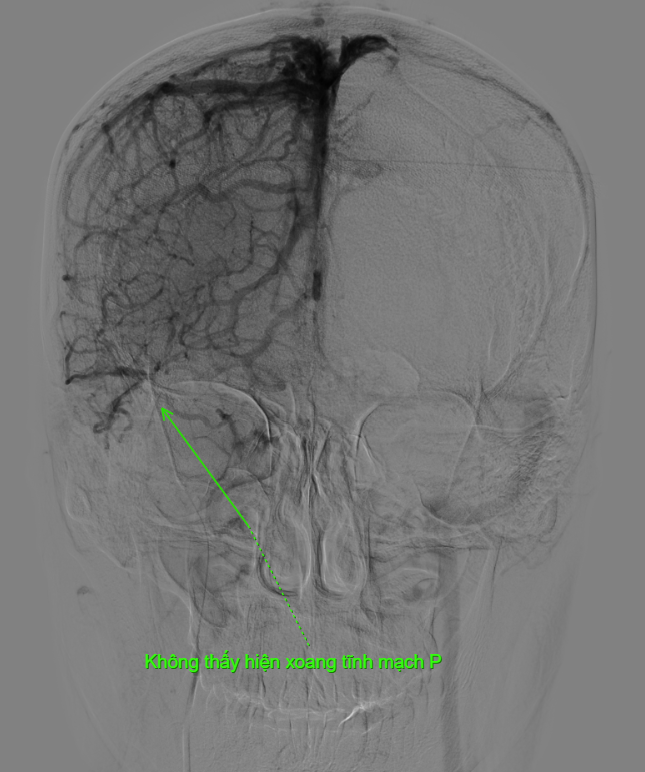

Kết quả phim chụp cho thấy bệnh nhân bị tắc gần như toàn bộ hệ thống tĩnh mạch dẫn lưu não, bao gồm xoang dọc trên, xoang ngang, xoang sigma và đoạn đầu xoang tĩnh mạch cảnh trong phải.

“Không giống như huyết khối động mạch, để lấy huyết khối tĩnh mạch não chúng tôi phải tiếp cận qua đường tĩnh mạch. Trước tiên, ê-kíp tiến hành chụp động mạch não để hiện hình hệ thống xoang tĩnh mạch và xác định vị trí huyết khối trên máy DSA. Sau đó, hệ thống dụng cụ được đưa từ tĩnh mạch đùi lên tĩnh mạch cảnh trong phải để lấy huyết khối từ tĩnh mạch cảnh trong lên đến xoang dọc trên - vị trí có huyết khối. Từ đây, chúng tôi lấy toàn bộ huyết khối từ xoang dọc trên xuống tĩnh mạch cảnh trong để tái thông hệ thống xoang tĩnh mạch não. Ca can thiệp kéo dài hơn 2 giờ đồng hồ. Ngay sau thủ thuật, dòng chảy trong hệ thống xoang tĩnh mạch được cải thiện rõ rệt, bệnh nhân giảm nhanh triệu chứng đau đầu và tránh được nguy cơ xuất huyết não, biến chứng nguy hiểm có thể xảy ra nếu xoang tĩnh mạch không được tái thông kịp thời”, bác sĩ Hải thông tin thêm.